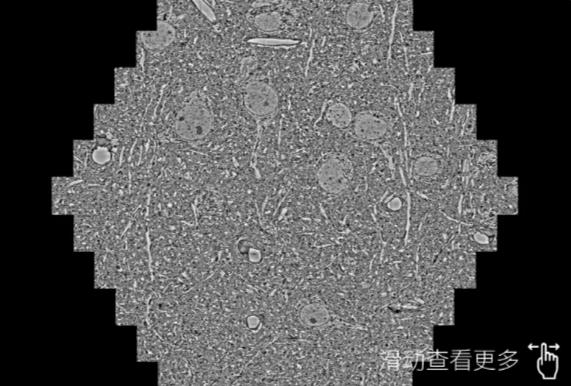

鼠脑切片。左图使用合肥蔡司合肥扫描电镜MultiSEM706对165μmx143pm面积区域成像,耗时仅需1.5秒。右图为鼠脑切片中30μm区域放大效果。样品由芝加哥大学B.Kasthuri提供。

使用蔡司高速合肥扫描电镜MultiSEM对1mm²人脑皮层组织进行高分辨成像,并对其中的各种细胞结构进行三维重构分析。左图展示了2x3mm²组织平面中锥体神经元的三维重构效果。右图显示了局部体积神经元三维重构。图像由哈佛大学chtman实验室提供,渲染图由D. Berger 制作。